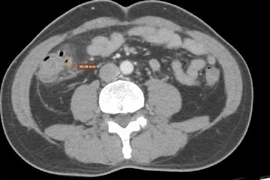

Bệnh nhân 58 tuổi đến khám bệnh viện vì đau bụng quanh rốn và mạn sườn phải, kèm theo đại tiện phân lỏng, kết quả chẩn đoán viêm túi thừa đại tràng.